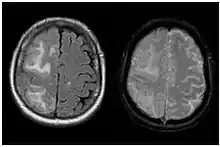

| Two MRI scans demonstrating the difference between ARIA-E (left) and ARIA-H in the parietal region (right) | |

Amyloid-related imaging abnormalities (ARIA) are abnormal differences seen in magnetic resonance imaging of the brain in patients with Alzheimer's disease. ARIA is associated with anti-amyloid drugs, particularly human monoclonal antibodies such as aducanumab.[1] There are two types of ARIA: ARIA-E and ARIA-H. The phenomenon was first seen in trials of bapineuzumab.[2]

ARIA-E

ARIA-E refers to cerebral edema, involving the breakdown of the tight endothelial junctions of the blood-brain barrier and subsequent accumulation of fluid.[3] In a double-blind trial of the humanised monoclonal antibody solanezumab (n = 2042), sixteen patients (11 taking the drug, 5 taking a placebo), or 0.78% developed ARIA-E. A further 7 patients developed ARIA-E during an open-label extension of the trial.[4]

ARIA-H

ARIA-H refers to cerebral microhaemorrhages (mH), small haemorrhages on the brain,[5] often accompanied by hemosiderosis.[1] mH are usually seen as small, round and low intensity lesions and are small haemosiderin deposits. Some studies define mH as being less than or equal to 10mm, while others define the cut-off as ≤ 5mm.[1] The prevalence of mH in healthy elderly people is approximately 6%, but this value increases to between 50% and 80% in elderly people with cerebrovascular disease.[6]